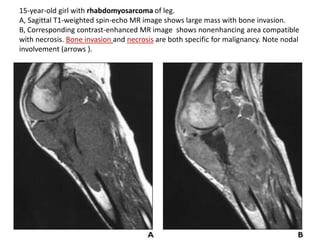

Introduction